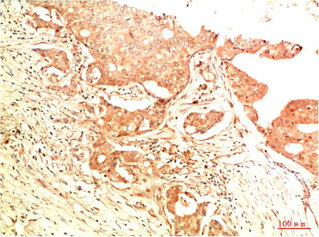

• Immunohistochemical analysis of paraffin-embedded Human Breast Carcinoma Tissue using Acetyl P53(K382) Mouse mAb diluted at 1:200.